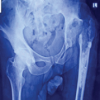

A 40-year male suffered significant trauma to his right thigh by slip and fall resulting in displaced reverse inter-trochanteric femur fracture with the ipsilateral shaft of femur fracture (Fig. 1). Skin traction followed by closed reduction and proximal femoral nailing was done on post-trauma day 7 with the patient in the supine position using traction and counter traction by the perineal post.